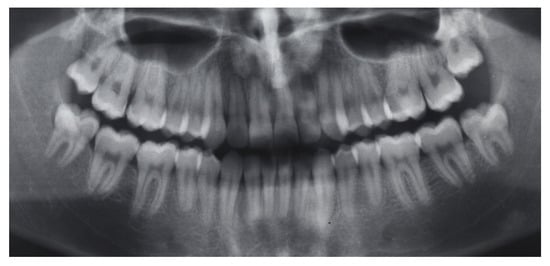

2.1. Diagnosis and Etiology

2.5. Results